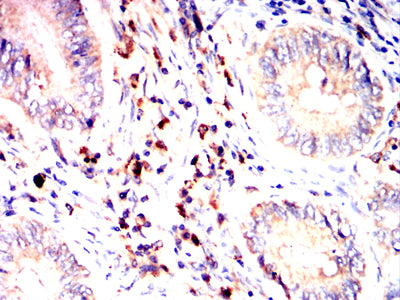

Product Image |

|